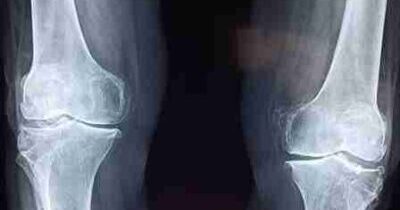

- Imaging tests: X-rays, CT scans, and MRI scans are the different types of imaging tests that help in obtaining a clear picture of the bone defect present in the knee region.